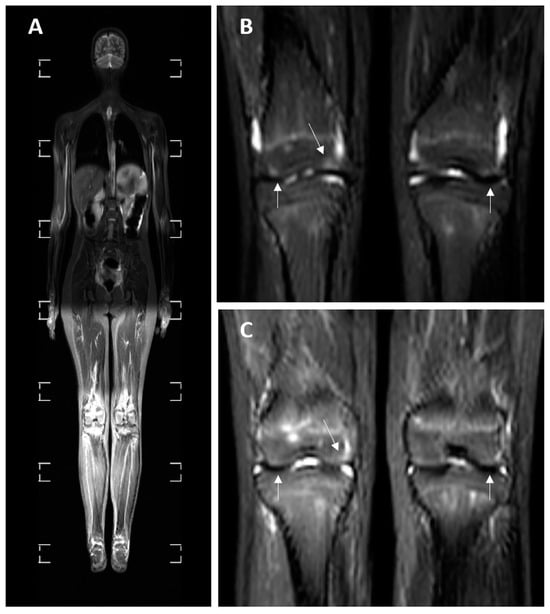

3.4. MRI Findings

| BME | 8 (24.24%) | 2 (22.22%) | 0 | 3 (42.86%) | 3 (30%) | p = 0.288 |

| Myositis | 10 (30.30%) | 1 (11.11%) | 6 (85.71%) | 1 (14.29%) | 2 (20%) | p = 0.004 * |

| Synovial fluid | 9 (27.27%) | 4 (44.44%) | 2 (28.57%) | 0 | 3 (30%) | p = 0.260 |